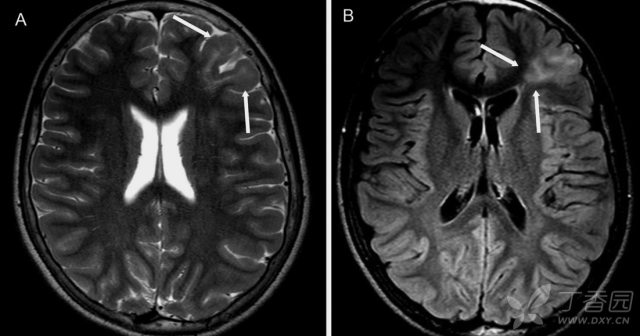

MRI 主要表现为局灶性皮质增厚,灰、白质分界模糊,白质异常信号,脑回形态异常,脑回白质萎缩,脑叶发育不全,邻近蛛网膜下腔扩大。FLAIR 及 T2WI 序列较为敏感,常表现为灰白质界限不清和皮质下白质高信号,可见病灶沿一个脑回的冠或脑沟的底向脑室延伸并逐渐变细,有学者将此现象命名为 Transmantle 征,常见于 FCD II 型。

图 2:34 岁 FCD 女性患者可见 Transmantle 征;A:T2WI 可见右侧额叶局部信号增高伴皮层增厚,灰白质界限不清;B:FLAIR 上可见条带状异常高信号从皮质延伸至侧脑室